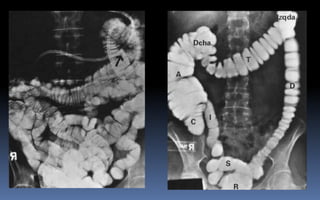

PROYECCION SIMPLE DE ABDOMEN

CRITERIOS DE EVALUACION P.S.A.

 Apreciar desde el abdomen

superior hasta la sínfisis del

pubis.

 Lumbares, pelvis y ultimas

costillas sin rotación.

 Apófisis espinosas en el

centro de cuerpos

vertebrales.

 Ver el bazo, riñones, psoas

y “borde inferior hepático

INTERPRETACION

 Estructuras óseas

(densidades).

 Tejidos blandos.

 Psoas.

 Bazo.

 Niveles Hidroareos.

 Intestino delgado.

 Colon.

 Silueta Renal.

PATRON AEREO DEL INTESTINO